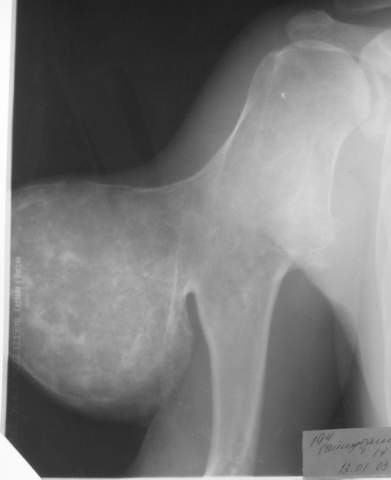

Вот, пришел сегодня утром на работу, фотоаппарат зачем то прихватил. ни о чем таком не думал, а там такоое... :-)

Мужчина, 27 лет, IQ вроде бы нормальный, из района, но не из деревни, а такую штуковину вырастил... аж жуть...